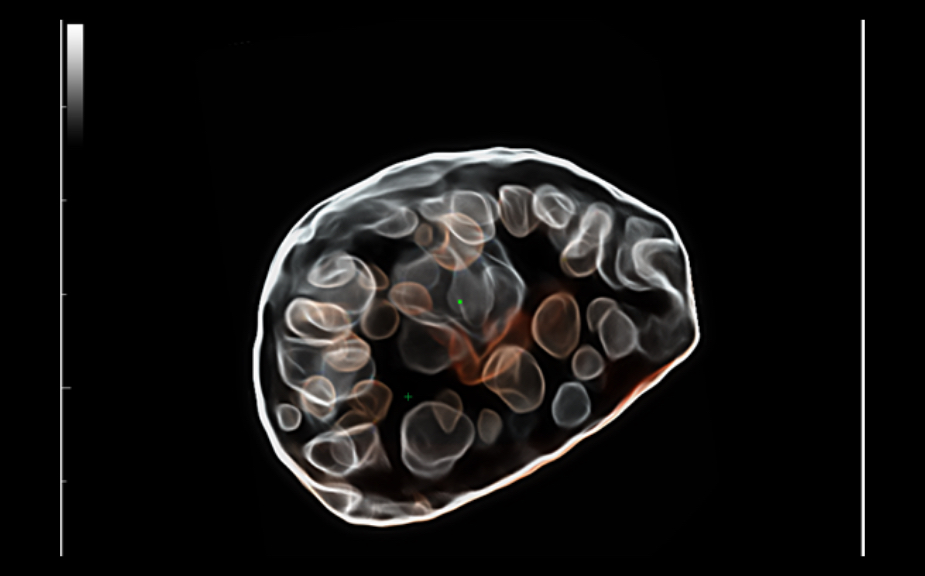

ImГЎgenes ClГӯnicas